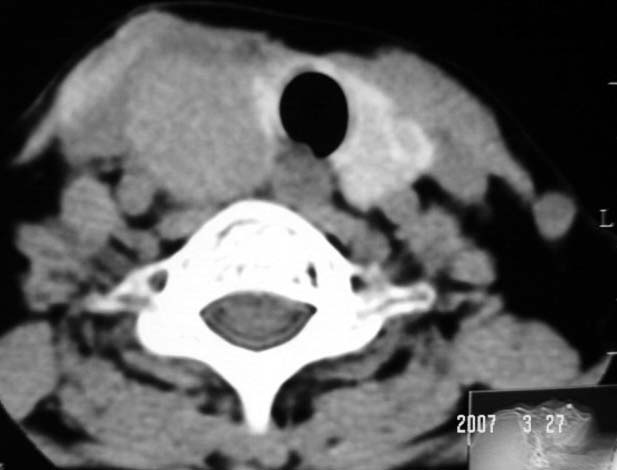

标题: CT7324:女57岁,右颈部肿物2年.

右侧甲状腺区均匀密度软组织肿块,无坏死及钙化,边缘光整,与周围组织分界清晰,病史较长,首先考虑右侧甲状腺腺瘤。